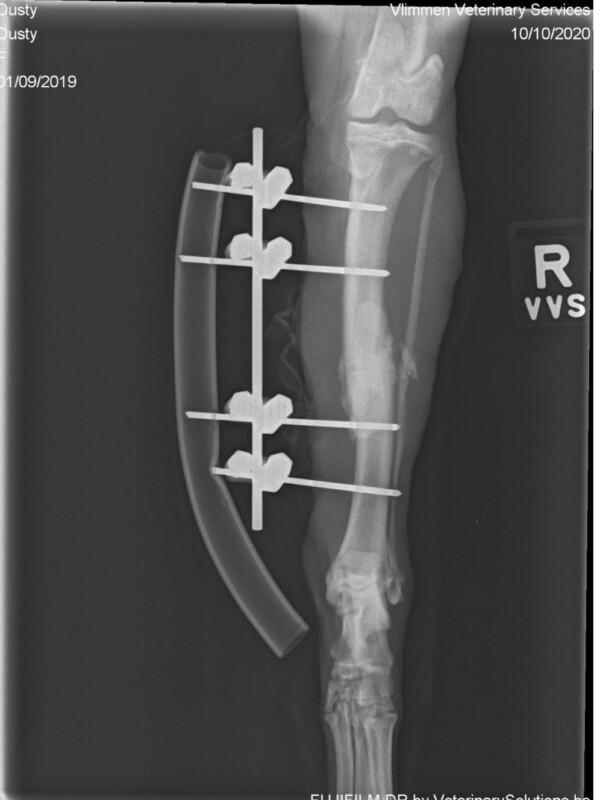

Dusty is een dochter van Angel.  Een pittig hondje. Ze heeft  tijdens het spelen haar achterpoot gebroken en na een operatie en pinnen is dat gelukkig goed genezen. Dusty speelt graag, is best bazig maar wil ook graag lekker geaaid worden. Ze wil graag bij vriendjes zijn, mensen of hondjes.  Ze is 1x geadopteerd geweest maar werd helaas terug gebracht.